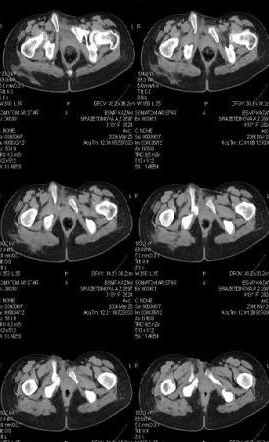

Предоставляю срезы. Если пациентку функционально ничего не беспокоит, стоит ли навязывать ей лечение.

Уважаемый Антон,

Если пациентка не собирается жить половой жизнью и вообще собирается в моностырь, то пожалуй, я бы согласился с Вами и навязывать лечение не стал.

Но если девочка более активна в жизни, я бы рекомендовал ликвидировать укорочение и вернуть тазу естественную форму.